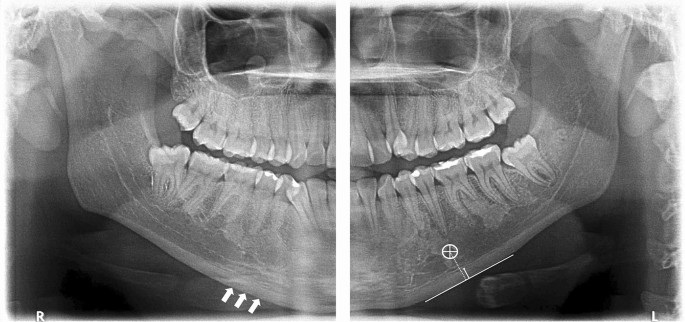

001 - Índices en la radiografía panorámica para la ayuda diagnóstica de osteoporosis - IDM